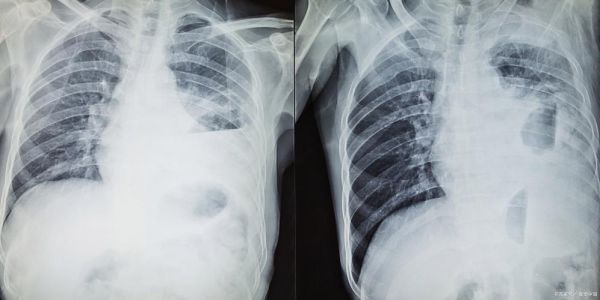

胸片提示“双肺纹理增粗”就一定是肺炎吗?

不是。纹理增粗在婴幼儿常见原因有:

- 生理性肺血偏多:出生后肺循环刚建立,血管影会比成人明显。

- 哭闹呼吸伪影:拍片时孩子大哭,肺泡短暂过度充气,血管被拉长显粗。

- 轻度病毒性感染:如呼吸道合胞病毒,胸片可仅表现为纹理增粗,听诊却仅有少许痰鸣。

只有当增粗纹理旁出现斑片状渗出影,且临床有发热、湿啰音,才考虑肺炎。